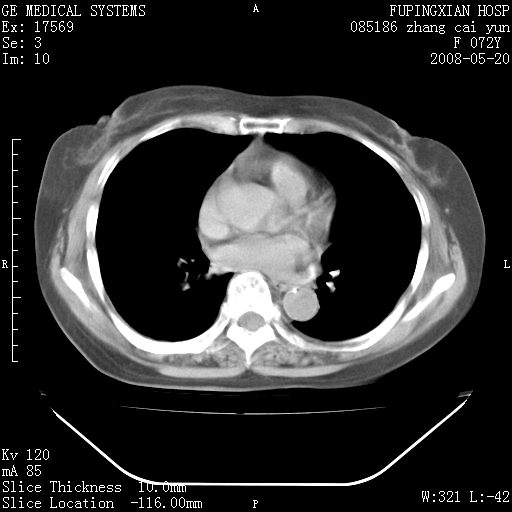

标题: CT13542:发热,咳嗽数日,经抗菌素治疗好转,请大家看排除 [打印本页]

标题: CT13542:发热,咳嗽数日,经抗菌素治疗好转,请大家看排除

上叶支气管略变窄并通畅,内壁光滑。考虑:单纯阻塞性肺炎!

右上叶支气管走行自然,未见明显管壁增厚等征像,另左主支气管起始部可见异常腔道向左侧延展左肺动脉干后方,与左下叶支气管相通,为左下叶支气管变异?

有节段性阻塞性肺炎与不张,近段支气管狭窄,周围散在肿大淋巴结影,以周围型肺癌可能性大,建议纤支镜检查。

右肺上叶实变影,内见支气管充气征,右上叶支气管通畅,肺门区未见软组织密度影,抗炎治疗有效,考虑炎症,建议继续抗炎治疗复查。

右上肺实变,间内有支气管充气征,考虑炎症,建议抗炎后复查